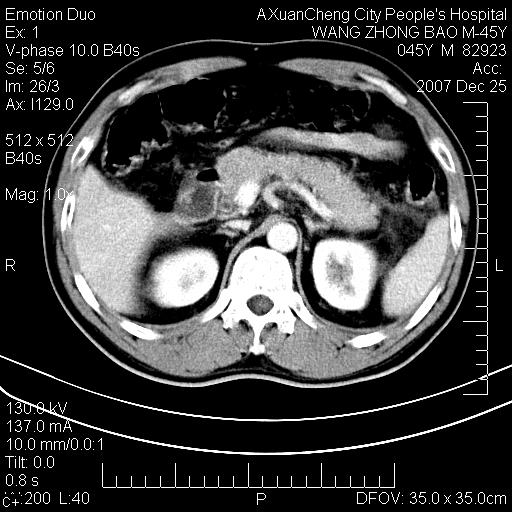

以下是引用卜一在2007-12-25 14:07:00的发言:[br]胰头钩部略增大,与十二指肠壶腹部关系密切,其内明显见软组织密度肿块,明显强化,但肠壁较光滑 柔软。考虑:炎性增生!建议消炎后复查!待除外壶腹部腺癌!

以下是引用zjzjr在2007-12-25 13:35:00的发言:[br]考虑正常的十二指肠乳头部,建议胃镜检查.

以下是引用qiuleiyu在2007-12-25 18:14:00的发言:[br]胰腺增大,周边渗出改变,肾前筋膜明显增厚,示少量积液.胆囊壁毛糙,周边少许渗出,胆总管壁厚,异常强化,然扩张不明显.结合病程急短;考虑;胆管炎,胆囊炎,胆源性胰腺炎可能大,请结合实验室检查及随访.

以下是引用lisihao在2007-12-25 14:23:00的发言:[br]急性水肿型胰腺炎[br]依据:1、胰腺弥漫性肿大,边缘稍毛糙;[br] 2、双侧肾周筋膜增厚,尤以左侧为甚(重要征象)[br] 3、双侧后胸膜增厚(刺激性炎症);[br] 4、结合病史,查血尿淀粉酶应该可以确诊。